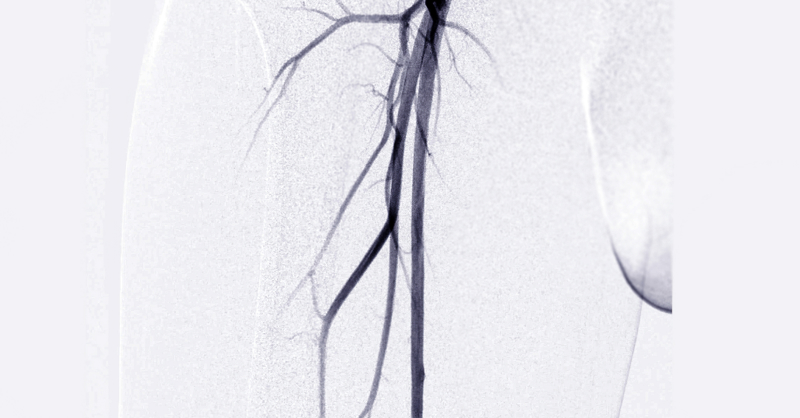

Arteriografías

Imágenes detalladas triplicadas de las arterias para diagnosticar y planificar tratamientos de manera más precisa y completa.